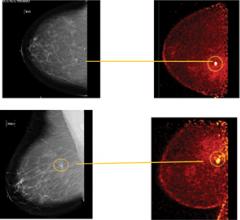

August 4, 2011 – Published last week in The American Journal of Roentgenology, researchers from Swedish Cancer Institute and the University of Washington used positron emission mammography (PEM) to find a correlation between fludeoxyglucose (FDG) uptake values and the prognostic factors that predict breast cancer survival. The highest FDG levels were in the most aggressive cancer type – triple negative cancers. Women with triple negative breast cancer have a higher mortality because there is no tailored therapy available to them. PEM may now benefit this patient population as it may help identify when a chemotherapeutic regimen is not working. PEM also has the potential to play a role in initial staging of breast cancer in patients at high risk for multifocal or multicentric disease who desire breast conservation therapy as an alternative to breast MRI.

Positron emission mammography (PEM), a high-resolution breast PET scanner, relies on differences in glucose metabolism to identify breast cancers from normal breast cells. Using PEM, we have an opportunity to find cancers at an even earlier stage than that detected with breast MRI, and we may even have the opportunity to find atypia because it changes cellular metabolism prior to the advent of neoangiogenesis. PEM has been shown in recently published prospective data to have similar sensitivity and superior specificity to breast MRI.